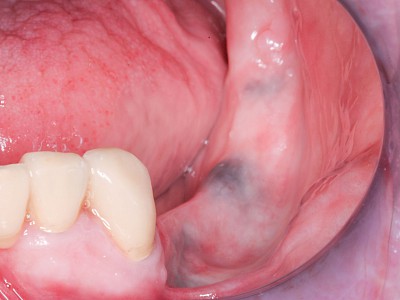

Pigmentstörung

Die Haut schützt sich gegen die UV-Strahlung der Sonne durch den Farbstoff Melanin. Dieses Pigment wird von den sogenannten (Melanozyten) in der oberen Hautschicht produziert. Pigmentstörungen können als Muttermal, Altersflecken aber auch als weiße Flecken auffallen.

Im Bereich der Schleimhaut kann es ebenfalls zu Pigmentbildungen kommen. Die Flecken sollten vor allem dann ärztlich untersucht werden, wenn sich diese Flecken spontan gebildet haben oder in Form, Farbe und Größe verändern. Es gibt auch allgemeine Erkrankungen, die ein gehäufte Anzahl von Pigmentflecken auf den Schleimhäuten zeigen.

Beispiele 9 Bilder